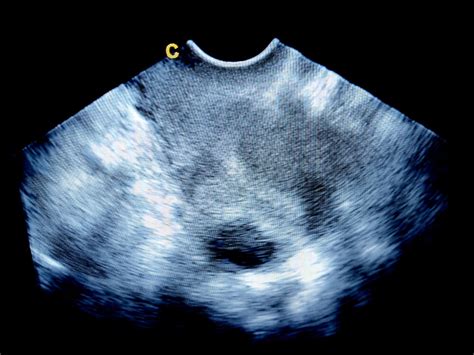

Kľúčovým nástrojom na diagnostikovanie hematómu je ultrazvukové vyšetrenie. Lekár dokáže pomocou ultrazvuku presne určiť veľkosť, polohu a prípadnú progresiu hematómu. Na základe týchto informácií, ako aj symptómov pacientky a jej tehotenskej anamnézy, stanoví lekár potrebný liečebný plán.

Po stanovení diagnózy hematómu je nevyhnutné pravidelné sledovanie. Odporúča sa kontrolný ultrazvuk každé 1 až 3 týždne, v závislosti od klinického stavu pacientky. Lekár monitoruje nielen veľkosť hematómu a jeho absorpciu, ale aj prietoky v uteroplacentárnych cievach a rast plodu. V prípade výrazného krvácania alebo objemného hematómu môže byť nariadená hospitalizácia s odpočinkom na lôžku. Pri vyššom štádiu tehotnosti sa môže pristúpiť k monitorovaniu vitálnych funkcií plodu pomocou kardiotokografie (CTG) a sonografie.